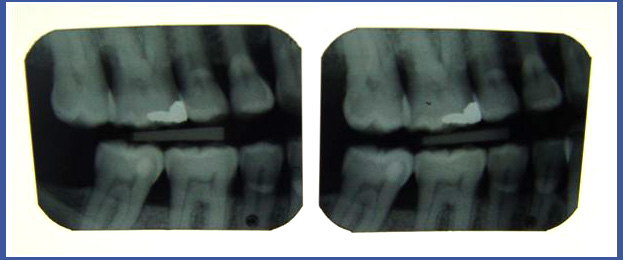

1. Снимки прикуса:

Обычно выполняются в стоматологической клинике – это снимок, который показывает коронки коренных зубов и клыков обеих челюстей на одном снимке (во многих случаях врачу будет достаточно двух маленьких снимков, выполненных на месте). Этот снимок позволяет нам увидеть кариозные полости в той части, которая расположена между зубами и на жевательных бороздках зубов! Обычно снимок делается во время обычной проверки у пациентов, у которых не существует проблем с рецессией костей и десен, а на зубах отсутствуют коронки! Если на зубах есть коронки, снимка прикуса будет недостаточно, и поэтому нужно выполнить рентгеновский снимок другого типа.